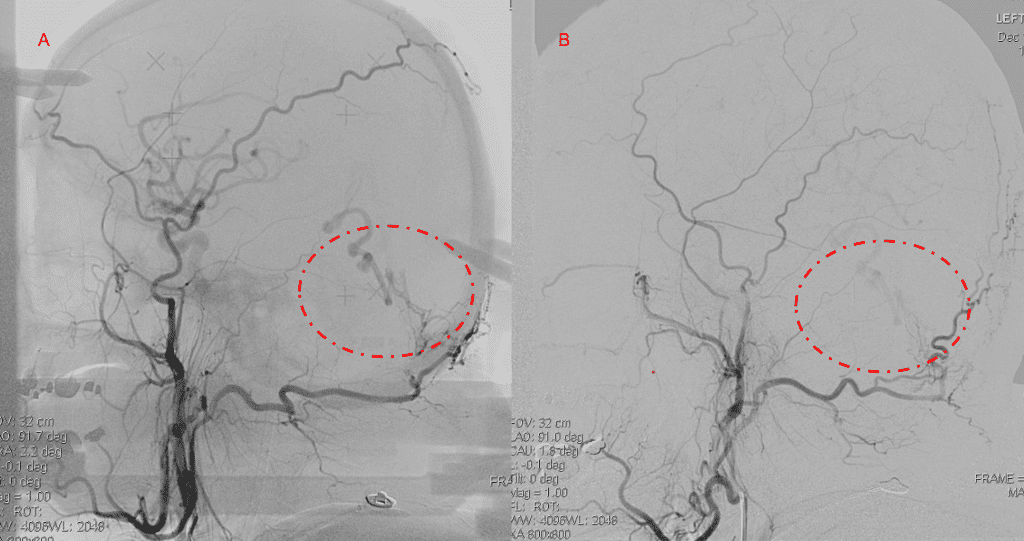

Figure 3. Right ECA AP and Lateral angiograms Pre (A and B) and Post NBCA embolization (C and D) Demonstrate near complete obliteration of right Occipital and Middle Meningeal Artery Fistulas